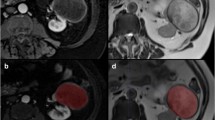

Solid renal masses (SRM) are difficult to differentiate based on standard MR features. The purpose of this study was to assess MR imaging features of SRM to evaluate performance of ensemble methods of classifying SRM subtypes.

MR images of SRM (n = 330) were retrospectively evaluated for standard and multiparametric (mp) features. Models of MR features for predicting malignant and benign lesions as well as subtyping SRM were developed using a training dataset and performance was evaluated in a test data-set using recursive partitioning (RP), gradient booting machine (GBM), and random forest (RF) methods.

In the test dataset, GBM and RF models demonstrated an accuracy of 86% (95% CI 75% to 93%) for predicting benign versus malignant SRM compared to 83% (95% CI 71% to 91%) for the RP model. RF had the greatest accuracy in predicting SRM subtypes, 81.2% (95% CI 69.5% to 89.9%) compared with GBM 73.4% (95% CI 60.9% to 83.7%) or RP 70.3% (95% CI 57.6% to 81.1%). Marginal homogeneity was reduced by the RF model compared with the RP model (P < 0.001), but not the GBM model (P = 0.135). All models had high sensitivity and specificity for clear cell and papillary renal cell carcinomas (RCC), but performed less well in differentiating chromophobe RCC, oncocytomas, and fat-poor angiomyolipomas.

Ensemble methods for prediction of SRM from radiologist-assessed image characteristics have high accuracy for distinguishing benign and malignant lesions. SRM subtype classification is limited by the ability to categorize chromophobe RCCs, oncocytomas, and fat-poor angiomyolipomas.